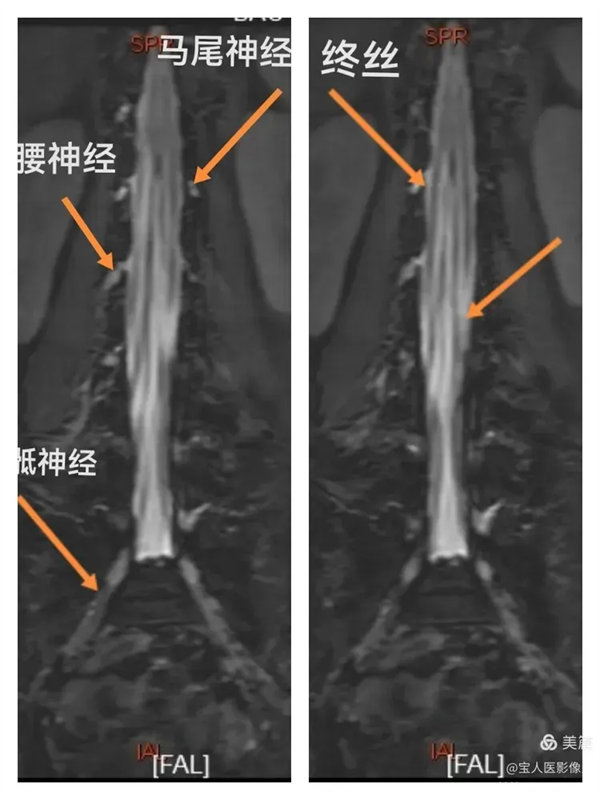

最大密度正面圖,顯示腰段腦脊液(高信號),其內的馬尾神經以及腰神經(線狀稍低信號)。

最大密度正面圖,顯示腰段硬膜囊內腦脊液(高信號),多條終絲(線狀稍低信號)縱向走行清晰。

最大密度正面圖,顯示腰段硬膜囊內腦脊液(高信號),多條終絲、腰神經及骶神經(線狀稍低信號)走行清晰。